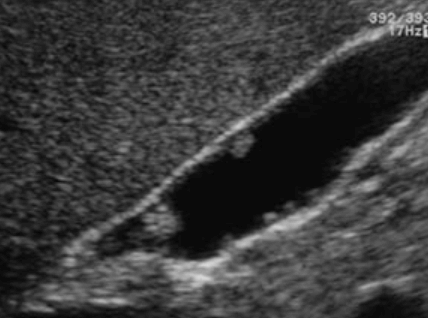

담낭 안에 결석이 존재하는 질환이다. 비정상적인 담즙의 정체와 감염에 의해 담석이 형성된다. 작은 담석은 담낭관의 폐쇄를 초래하므로 담석의 수가 많고 크기가 작을수록 위험하다. 비만(fat), 다산(fertile), 여성 또는 나이가 많을수록 발생 확률이 높다. 증상은 우상복부통증, 오심과 구토 등이 나타난다. 담석의 성분은 cholesterol, calcim bilirubin, calcium carbonate이며 대부분 bilirubin 또는 cholesterol이다.

- 강한 고에코의 반사체 (strong echogenic sign)

- 후방음향음영 (posterior acoustic shadow)

- 환자 체위에 따라 움직임 (rolling stone sign)

- Wall-echo-shadow (WES) triad = double arc shadow sign

- 콜레스테롤 결석은 강하고 선명한 후방음영이 존재한다

- 색소성 결석은 후방음영이 없다 (체위 변화로 용종과의 감별 필요함)

- Color doppler 적용 시 twinkle artifact 가 보인다